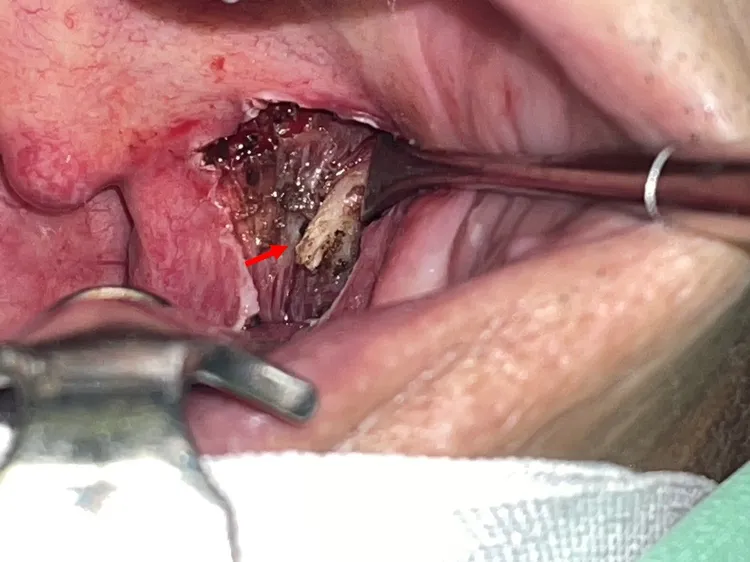

男子扁桃腺後方的扁桃窩,出現不該有莖突(箭頭),這根骨頭讓男子喉嚨老是卡卡的,吞嚥不順。侯思任醫師提供

手術時,侯思任摘除掉男子左側扁桃腺、翻開肌肉,發現男子扁桃腺後方的扁桃窩,有根白白的骨頭,其實這是位在耳道下方的莖突,這根骨頭因鈣化等因素往前傾或長度太長,長到扁桃腺後方,「這一帶有很多神經血管,一旦(有骨頭)壓迫,就可能出現喉嚨痛或卡卡、轉脖子痛、頭痛、耳朵痛等不適。」

這根骨頭讓男子喉嚨老是卡卡的,吞嚥不順。侯思任醫師提供